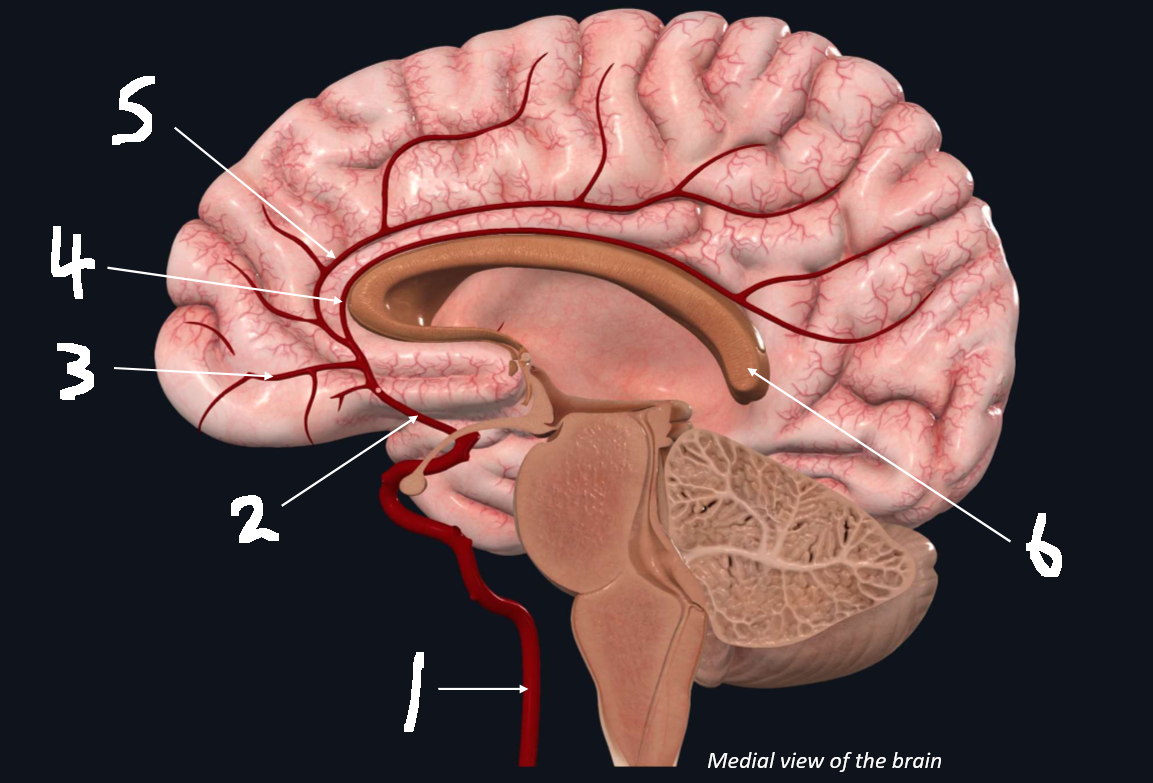

What is 1?

internal carotid artery

What is 2?

anterior cerebral artery

What is 3?

frontopolar artery

What is 4?

pericallosal artery

What is 5?

callosomarginal artery

What is 6?

corpus callosum